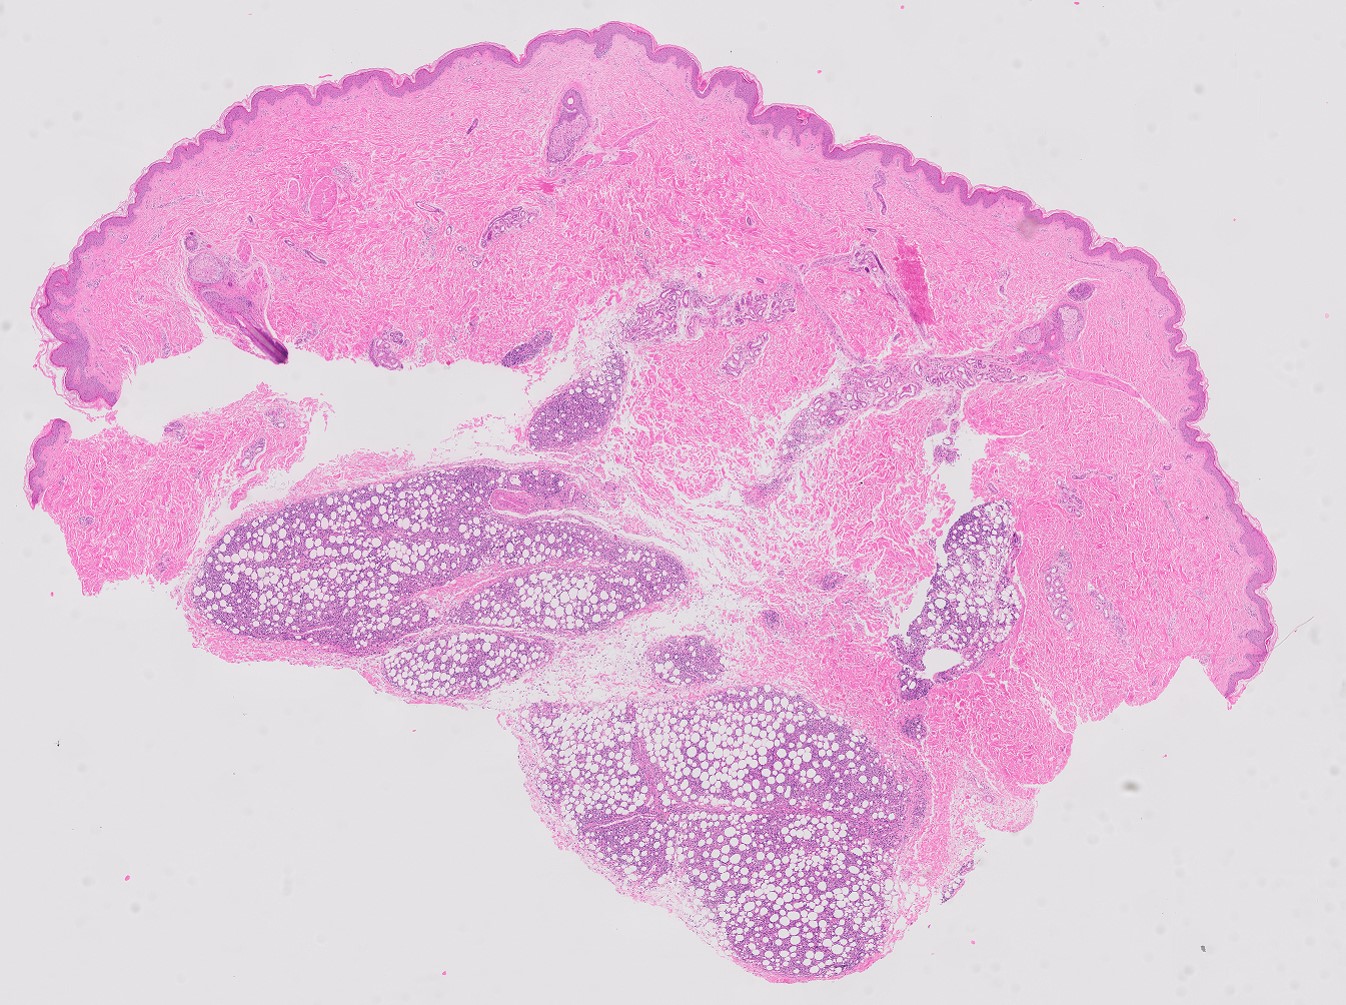

Subcutaneous panniculitis-like T-cell lymphoma PA subcutaneous panniculitis-like T-cell lymphoma

SPTL histologisch beeld

PA-foto's: dr. E.J. Kooi, patholoog, Afdeling Pathologie, Amsterdam UMC.